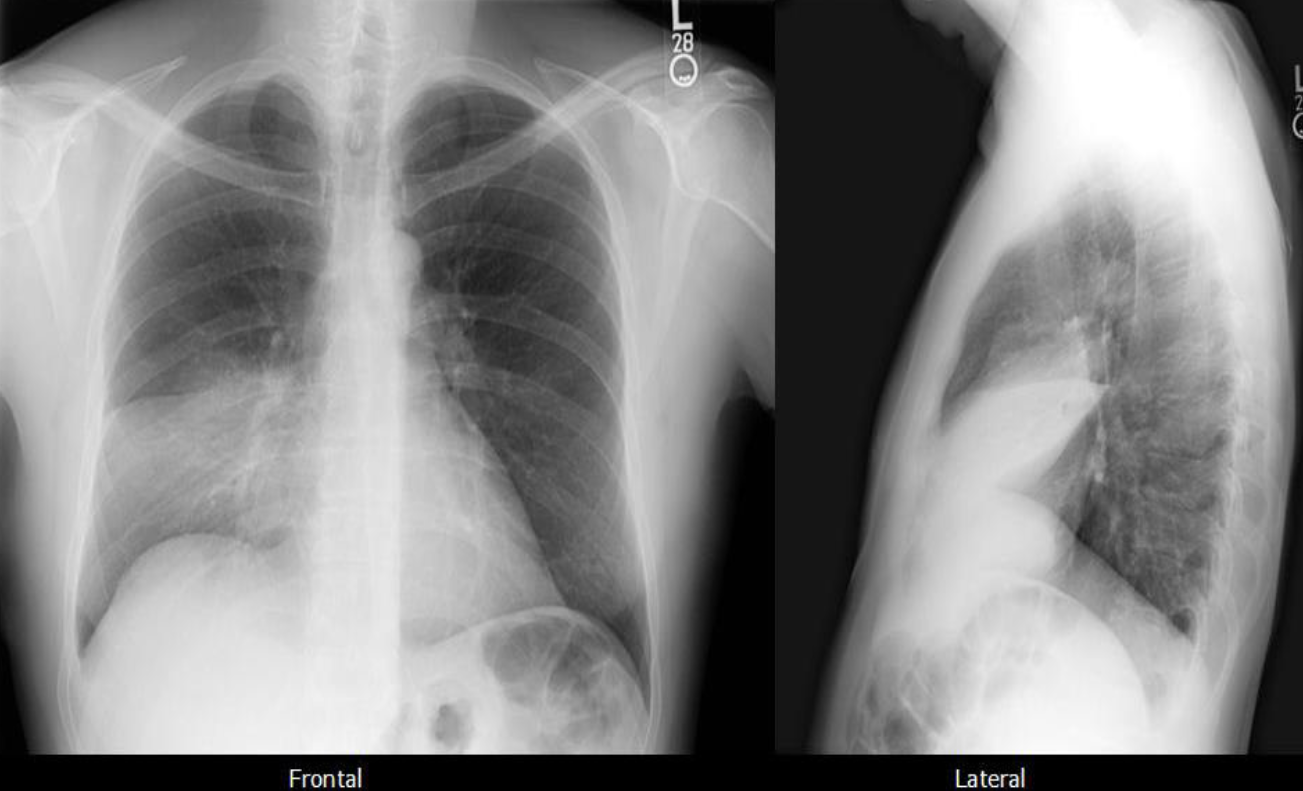

A. What is the most likely diagnosis in the given images; RT lower lobe pneumonia

B. Which lobe of the lung affected by this disease in the given image. Lower lobe, reverse change of opacity from spine

A. What is the most likely diagnosis in the given images

pneumonia ex… due fever cough and the imaging

B. Which lobe of the lung affected by this disease in the given image. Right middle Lobe Lesion, due obliteration of diaphragm - and lateral of horizontal fissure opaque